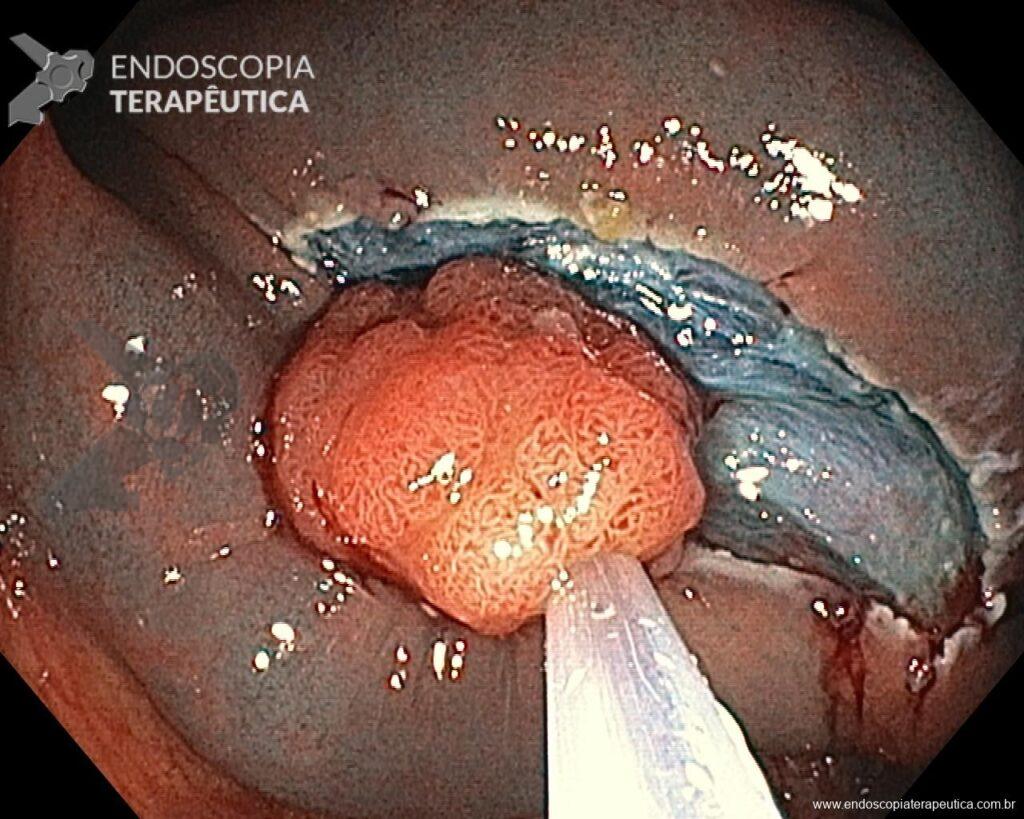

– Lesión plano-elevada de crecimiento lateral (LST), del tipo granular homogénea (LST-G-H), con superficie y vasculatura regulares a la cromoscopia virtual con NBI, midiendo cerca de 4cm, localizada en el ciego (París 0-IIa / JNET 2A).

En vista de lo anterior, para el caso ejemplificado anteriormente, se optó por la resección mediante la técnica EPMR, tanto por el tipo morfológico (LST-G-H) y las características superficiales de la lesión (JNET 2A), como por su ubicación (ciego), que presenta un mayor riesgo de complicaciones.